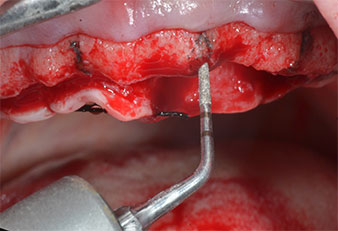

Uno strumento piezoelettrico (Piezomed I1) a forma di fiamma, rivestito in diamante, è stato usato per contrassegnare le posizioni dell'impianto e per eseguire una preparazione pilota (Fig. 3). Si è prestato attenzione a utilizzare un movimento verticale ascendente e discendente, con potenza ridotta, irrigazione completa e bassa pressione (inferiore a 300 g). Successivamente è stato applicato uno strumento pilota (Piezomed I2A/I2P) per l'ingrandimento iniziale delle sedi dell'impianto del diametro di 2 mm (Fig. 4), seguito da un inserto da 3 mm (Fig. 5).